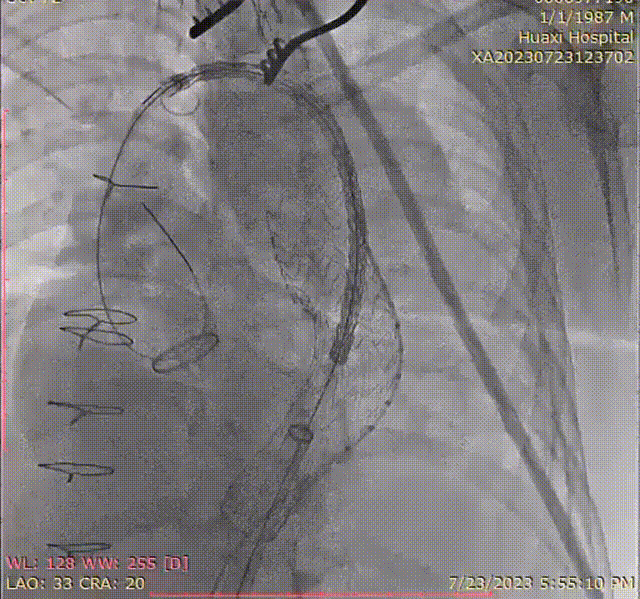

4. 继续送入近端GORE® TAG® 可主动调控胸主动脉覆膜支架TGMR313120,顶住导丝以左颈总后缘定位。

gore医疗怎么样「胸有乾坤」可调可控 精准出击——四川大学华西医院肖正华教授团队:CADS治疗B型主动脉夹层病例分享_https://www.jmylbn.com_新闻资讯_第22张

CADS支架定位

gore医疗怎么样「胸有乾坤」可调可控 精准出击——四川大学华西医院肖正华教授团队:CADS治疗B型主动脉夹层病例分享_https://www.jmylbn.com_新闻资讯_第23张

CADS释放前回撤鞘

5. CADS第一阶段释放,支架从近端向远端打开,释放至50%直径。

gore医疗怎么样「胸有乾坤」可调可控 精准出击——四川大学华西医院肖正华教授团队:CADS治疗B型主动脉夹层病例分享_https://www.jmylbn.com_新闻资讯_第24张

6. 支架近端位置微调后,再次顶住导丝,二次释放。

gore医疗怎么样「胸有乾坤」可调可控 精准出击——四川大学华西医院肖正华教授团队:CADS治疗B型主动脉夹层病例分享_https://www.jmylbn.com_新闻资讯_第25张

术中小弯侧定位造影

gore医疗怎么样「胸有乾坤」可调可控 精准出击——四川大学华西医院肖正华教授团队:CADS治疗B型主动脉夹层病例分享_https://www.jmylbn.com_新闻资讯_第26张

CADS释放一半后近端位置调整